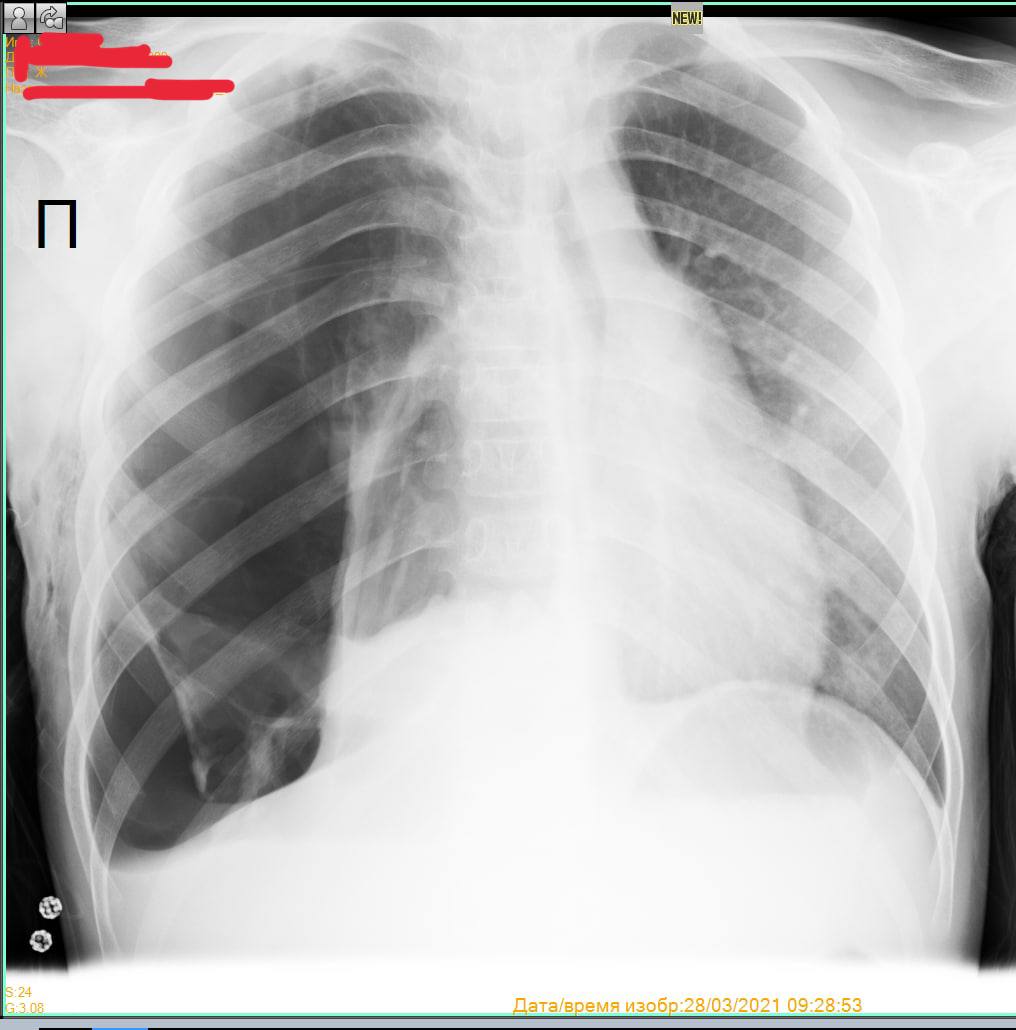

Пневматоракс . Диафрагмаль грыжа

симптом плаща, коллапс правого лёгкого